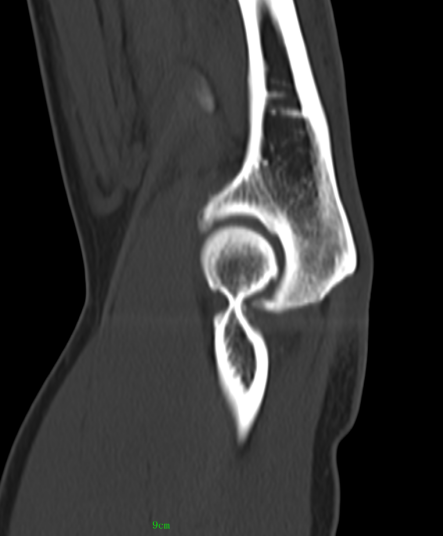

近日,一位52岁的男性患者,因右肘疼痛伴活动受限2周余来pilipili 就诊。经检查,确诊为肘关节骨性关节炎伴游离体。患者于入院第二天在气管插管麻醉下行右肘关节镜探查+滑膜切除+游离体取出术。术后症状明显缓解,疼痛减轻,关节活动范围改善,现已成功出院。

患者鹰嘴骨质增生;前侧关节腔游离体形成

术后CT、DR提示游离体取出